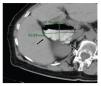

¿ Figura 1. Imagen tomográfica de un Dd de base estrecha.

En 43 casos (86%) se evidenció Dd único: un caso (2%) en la primera porción, 13 (26%) en la segunda, 24 (48%) en la tercera y cuatro (8%) en la cuarta porción duodenal En ocho pacientes (16%) se identificaron Dd múltiples: siete casos (14%) en la segunda y tercera porciones y un caso con Dd concomitantes con divertículos yeyunales En 16 pacientes (27%) se encontraron divertículos colónicos concomitantes. El diámetro promedio de los Dd fue de 2.5 cm (rango 0.9 cm a 7.1 cm) (Figuras 2 y 3).

¿ Figura 2. Imagen tomográfica de un Dd de 0.9 cm de diámetro.